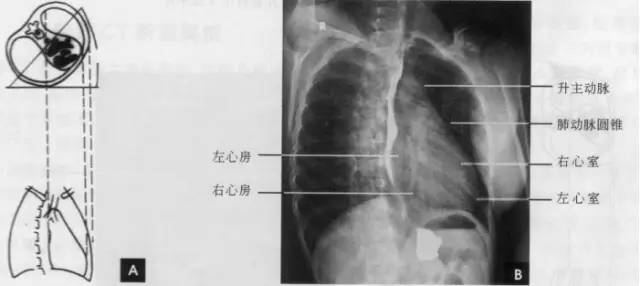

心脏和大血管在平片上的投影彼此重叠,仅能显示各房室和大血管的轮廓,不能见到其内部结构和分界。因此,必须用不同的位置投照,才能使各个房室和大血管的边缘显示出来。常用后前位、右前斜位、左前斜位和左侧位的摄影,分述如下:

(一)后前位

正常心影2/3位于中线左侧,1/3位于右侧,心尖指向左下,心底部朝向右后上方,形成斜的纵轴。后前位心脏大血管有左右两缘:心右缘分为两段,上段为升主动脉与上腔静脉的总合影,在幼年和青年人边缘主要为上腔静脉影向上延伸,在老年人常见纡曲延长的升主动脉影突出于上腔静脉边缘之外;心右缘下段为右心房所构成,有时在心瞩角内可见一向外下方倾斜的三角形影,为下腔静脉攻肝静脉影,深吸气时明显。心左缘分为三段,上段为主动脉弓;中段为肺动脉主干,但偶尔可为左稀动脉构成,称肺动脉段或心腰,此段较低平或稍突出:下段由左心室构成,左心室在下方形成心尖。左心室与肺动脉之间有长约10cm的一小段,由左心耳构成,正常时不能与左心室区分。透视下左心室与肺动脉段的搏动方向相反,两者的交点称相反搏动点,该点上下两侧心缘里“翘翘板”样运动,该点位置是衡量左右心室增大的一个重要标志。肥胖人左心膈角常有脂肪垫充填,为密度较低的软组织影。后前位能了解心胸及肺循环概况,正常人心(h1+h2)胸(t)比率不大于0.5(如下图)。

(右前斜位)

标准右前斜位(又称第一斜位)为后前位向左旋转约45。所得影像。心前缘自上而下由主动脉弓曼升主动脉、肺动脉、右心室漏斗部、右心室前壁和左心室下端构成。升主动脉前缘平直,弓部则在上方弯向后行;肺动脉段和漏斗部稍为隆起;心尖以上大部分为右心室构成。心前缘与胸壁之间有尖向下的三角形透明区称为心前间隙。心后缘上段为左心房,下段为右心房,两者无清楚分界。心后缘与脊柱之间透明区称心后间隙,食管在心后间隙通过,钡剂充盈时显影。右前斜位主要观察右室流出道及左心房大小(如下图)。

(三)左前斜位

从后前位向右旋转约60。得到左前斜位(又称第二斜位).此时室间隔与中心x线接*平近**行。因此.两个心室大致是对称的分为两半,前方一半为右心室.后方一半为左心室。心前缘上段为右心房.下段为右心室,右心房段主要由右心耳构成,房室分界不清。右心房影以上为升主动脉,两者相交成钝角:心后缘可分为上下两段,上段由左心房,下段则由左心室构成。左心室段的弧度较左心房大,两个不同弧度的交接点,可作为两者的分界。通过主动脉窗可兄气管分叉,主支气管和肺动脉,左主支气管下方为左心房影。左前斜位可了解各房室和主动脉情况(如下图)。

(四)左侧位

心影从后上向前下倾斜,心前缘下段为右心室前壁,上段则由右心室漏斗部与肺动脉主干构成,再苣上为升主动脉前壁,直向上走行。这些结构与翦髓壁之间的三角形透亮区称为胸骨后区。心后缘上中段由左心房构成,下段则由左心室构成。心后下缘、食管与膈之间的三角形间隙,为心后食管前间隙(如下图)。